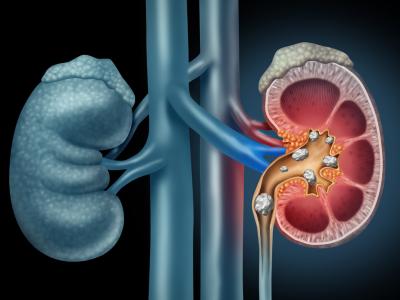

यह गुर्दे की पथरी के विकास के जोखिम को कम कर सकता है। गुर्दे की पथरी के कारणों में से एक कम मूत्र साइट्रेट है लेकिन नियमित रूप से फल और सब्जियां खाने से विशेष रूप से खट्टे फल मूत्र साइट्रेट के स्तर को बढ़ा सकते हैं। जिससे किडनी में पथरी होने का खतरा कम हो जाता है।